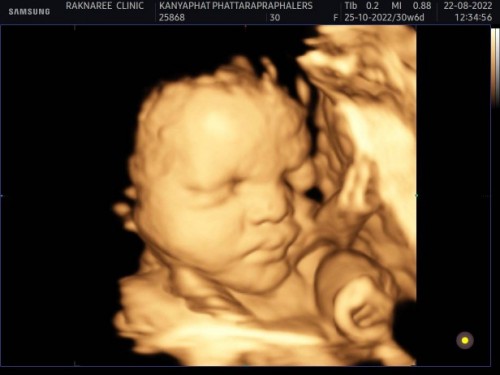

ขอดูหน้าทีมเดือนตุลาคมหน่อยจ้าา33+2แล้วนับวันรอผ่าแล้วคจ้าาา#หนูเป็นเด็กผู้หญิงค่ะ💓

บ้านนี้ซาวด์ 4D ตอน 26 weeks ค่ะ ตอนนี้ 38 5 weeks นัดผ่า 10/10/65 นี้ค่ะ ตื่นเต้นมากๆ 😁😍